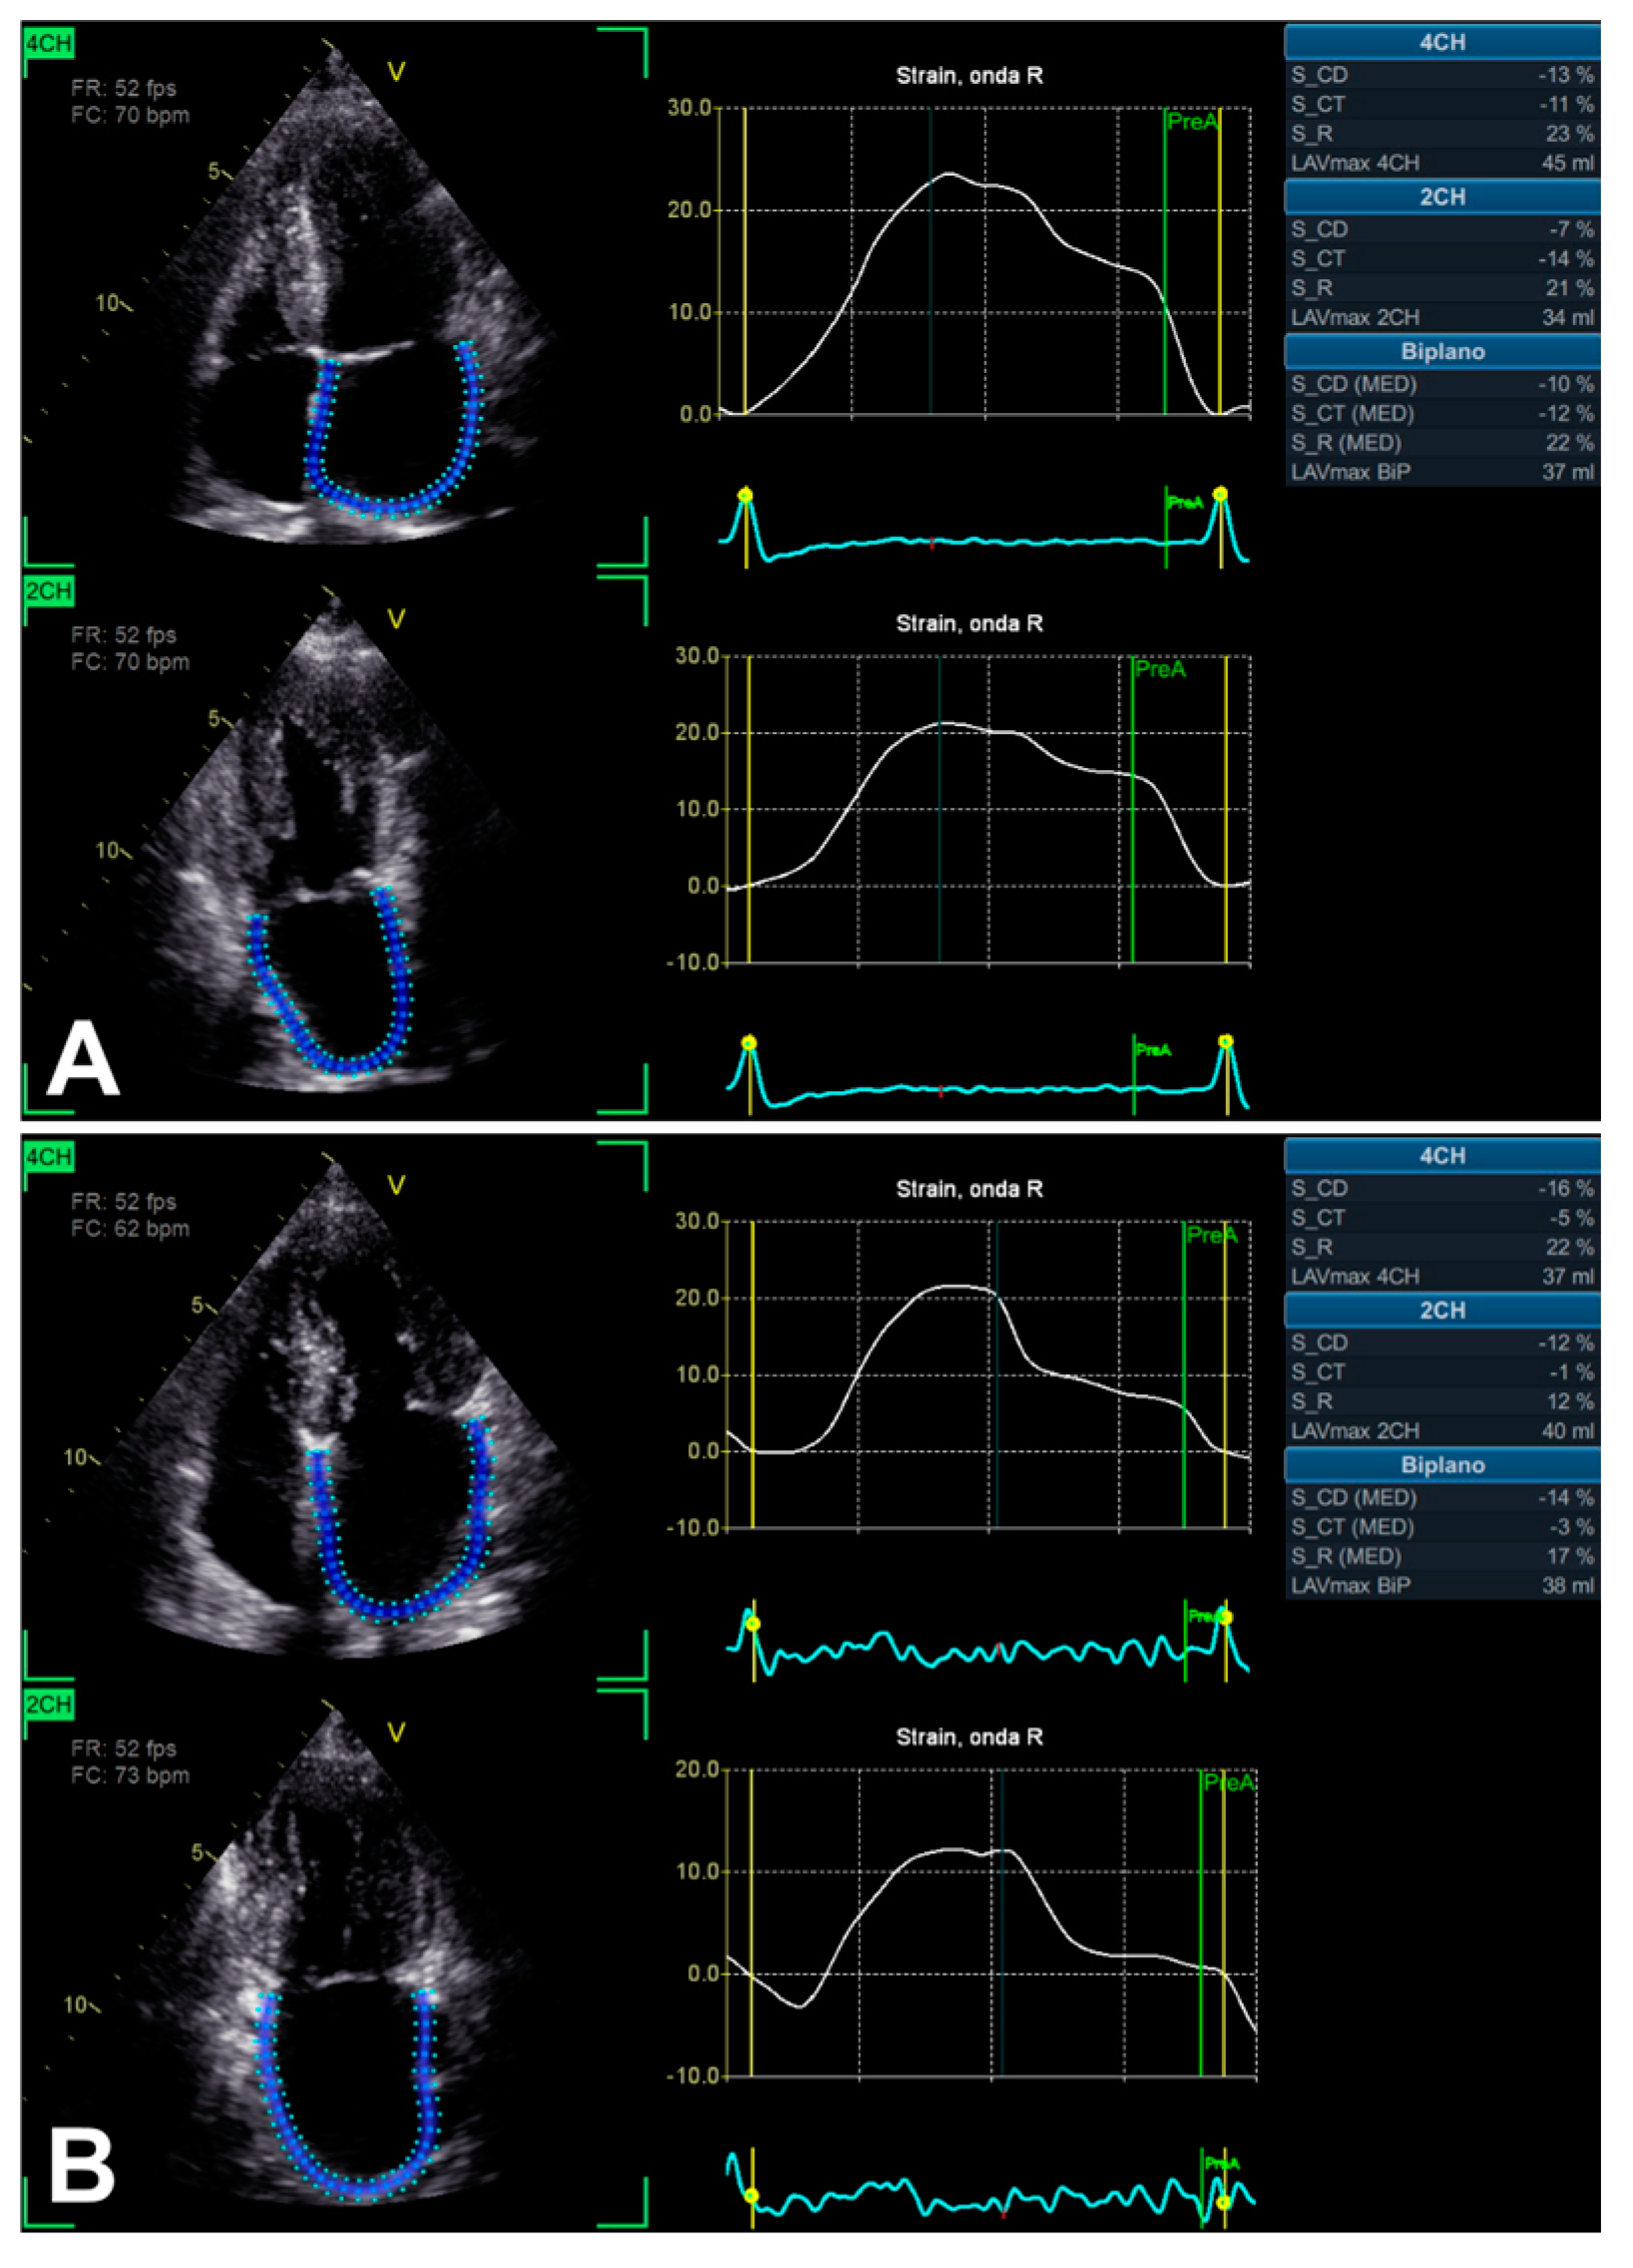

3.2. Left Atrium Strain